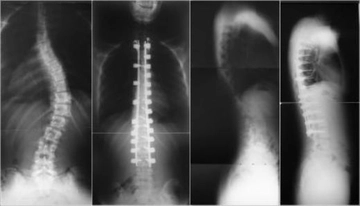

Skolyozun tanısı genellikle fizik muayene ve görüntüleme yöntemleri ile konulur.

• Fizik muayene sırasında doktor, omurganın görünümünü değerlendirir ve belirtileri inceler.

• X-ray, skolyozun derecesini belirlemek için en yaygın kullanılan görüntüleme yöntemidir.

• Gerekirse, MRI veya CT taramaları ile daha detaylı bilgi edinilebilir.

Bu yöntemler, skolyozun ciddiyetini ve tedavi gereksinimlerini belirlemede kritik öneme sahiptir.

• Cerrahi müdahale: Şiddetli skolyoz vakalarında, omurganın düzeltilmesi için cerrahi operasyon gerekebilir.